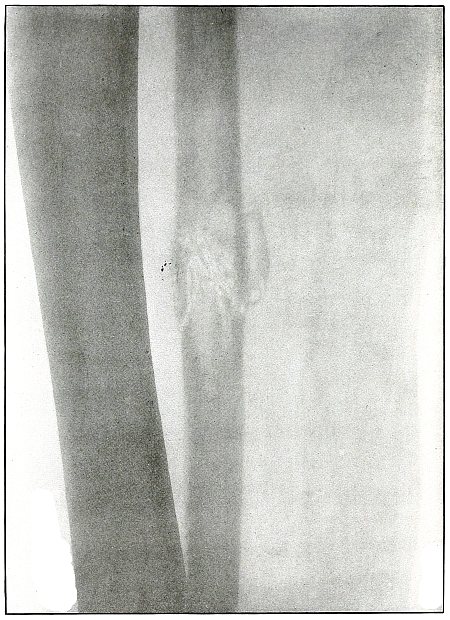

Gunshot fracture, tibia |

134 |

| 63. |

Gunshot fracture, tibia |